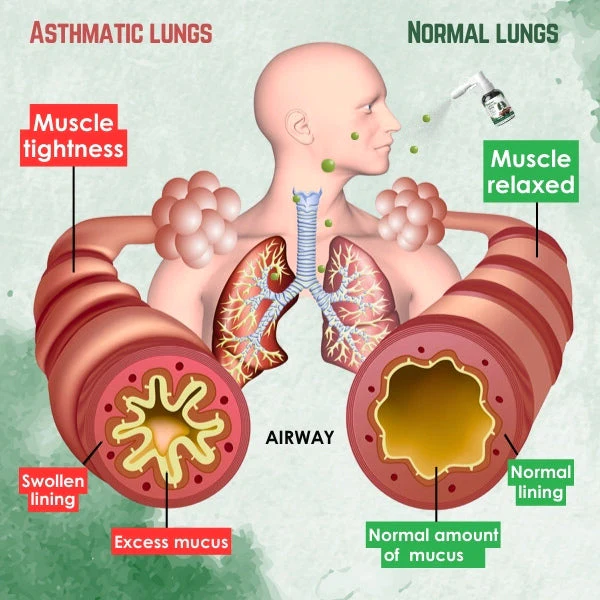

Crafted with precision from natural plant extracts, this innovative spray delivers soothing relief and improved lung function by effectively clearing mucus and waste, thus promoting optimal respiratory well-being.

Respira™ Lung Care Spray employs an advanced delivery mechanism, emitting a fine mist directly into the airways for optimal results. Upon application, the gentle mist coats the respiratory system precisely, ensuring targeted action. This approach maximizes the spray’s efficacy, fostering lung health and thorough respiratory cleansing.